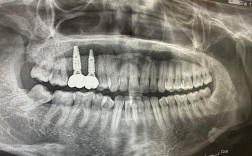

- 检查牙龈状况、探诊深度、出血指数、种植体动度、拍X光片评估骨状况,进行专业种植体洁治,清除日常清洁难以到达的菌斑和结石。